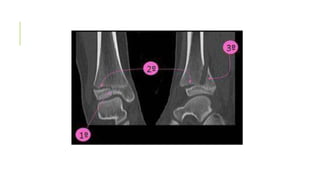

CLASIFICACIÓNDESALTER- HARRIS

Tipo 3 poco frecuente

•Se extiende desde la superficie articular hasta la

zona profunda de la placa epifisiaria y luego a lo

largo de esta hasta la periferia.

•Cizallamiento a nivel intraarticular

•Epífisis distal de la tibia

•En adolescentes, una parte de la placa epifisiaria

ya se ha cerrado y otra aun permanece abierta.

•“Fractura triplana”

intraarticular

Tipo 3

•Reducción abierta y fijación interna para restaurar

perfectamente la superficie articular normal

•Pronóstico bueno siempre y cuando no se afecte

el aporte sanguíneo a la porción separada de la

epífisis.